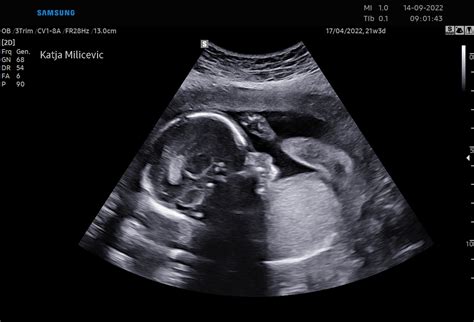

Pogosto se pojavljajo vprašanja o velikosti nosečniškega trebuha, zlasti v zgodnji nosečnosti. Kot je v enem izmed forumov pojasnil mag. Stanko Pušenjak, dr. med., specialist ginekolog in porodničar, trebuh v prvi tretjini nosečnosti in celo v prvi polovici še ne prispeva toliko k prostornini trebušne votline, da bi se ga lahko opazilo. K povečanju trebuha pred 20. tednom nosečnosti predvsem prispevajo slaba prebava, kopičenje črevesnih plinov, včasih pa tudi pridobivanje maščobe ter zadrževanje vode. Poleg tega se medvretenčne ploščice in sklepi zmehčajo, kar povzroči, da se hrbtenica v ledvenem delu začne »kriviti« naprej (lordoza), kar povzroči izbočenje trebuha in značilno nosečniško držo. Zaradi same velikosti maternice vaš trebuh niti malo ni povečan.

Velikost nosečniškega trebuha ne more razkriti velikosti otroka. Ginekolog bo tekom nosečnosti redno meril velikost trebuha in rast otroka. Meritve lahko tudi nihajo, saj ima lahko dojenček v enem mesecu pri rasti velik poskok, spet v drugem mesecu pa zraste manj. Vendar pa velikost otroka ne nakazuje velikosti trebuha in obratno. Pomembna je namreč tudi količina plodovnice, ki se lahko giblje od 300 mililitrov do 1500 mililitrov.

Tretje trimesečje se začne v 28. tednu nosečnosti in traja do poroda, okoli 40. tedna. V tem obdobju plod znatno zraste, iz približno 700 gramskega in 40 cm dolgega ploda v 3000 gramskega in 52 cm dolgega dojenčka. Kosti se med 7. in 8. mesecem transformirajo iz hrustanca v kost. Do 32. tedna nosečnosti dojenčkova koža ne bo več prosojna. Do 29. tedna bo dojenček že popolnoma razvil čutilo za tip. Do 31. tedna bo dobival signale iz vseh 5 čutil. Dojemanje sveta se nadaljuje, dojenček zaznava zvok že v trebuhu in po rojstvu prepozna očetov glas. Okoli 34. tedna se otrok obrne. V kolikor se otrok samostojno ne obrne do 37. tedna, vas bodo napotili na posvet k porodničarju, kjer se boste dogovorili za način poroda in morebitni zunanji obrat ploda na glavico.